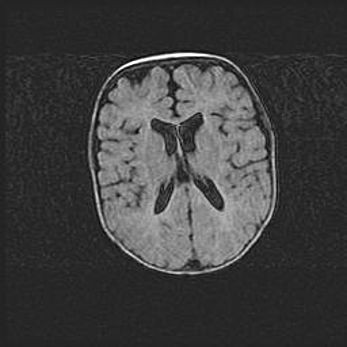

Открытая гидроцефалия.

Возраст: 9 месяцев 12 дней

Вес: 6800 г

Пол: мужской

Окружность головы: 41,5 см

Срок гестации: 28 недель

Гидроцефалия головного мозга у новорожденных имеет характерный признак: опережающий рост окружности головы приводит к визуально хорошо определяемой гидроцефальной форме сильно увеличенного в объёме черепа. Детские неврологи определяют следующие симптомы гидроцефалии у грудничков: выбухающий напряжённый родничок, частое запрокидывание головы, смещение глазных яблок к низу.